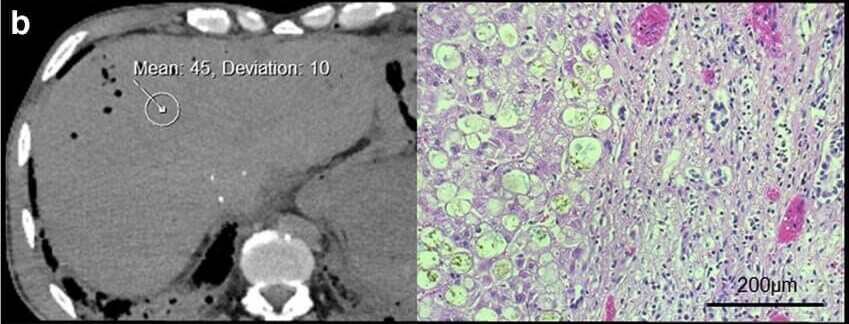

Publications Pathology Liver Pathology Int J Legal Med . 2019 Nov;133(6):1861-1867. doi: 10.1007/s00414-019-02016-1. Epub 2019 Feb 20. Read Publication here Liver Pathology Int J Clin Oncol . 2002 Apr;7(2):128-32. doi: 10.1007/s101470200018. Read Publication here Abdominal Pathology Arch Med Sadowej Kryminol . 2019;69(1-2):40-55. doi: 10.5114/amsik.2019.89235. Read Publication here Liver Pathology Int J Comput Assist Radiol Surg . 2017 Feb;12(2):205-221. doi: 10.1007/s11548-016-1481-5. Epub 2016 Sep 22. Read Publication here Liver Pathology Int J Legal Med . 2019 Nov;133(6):1861-1867. doi: 10.1007/s00414-019-02016-1. Epub 2019 Feb 20. Read Publication here